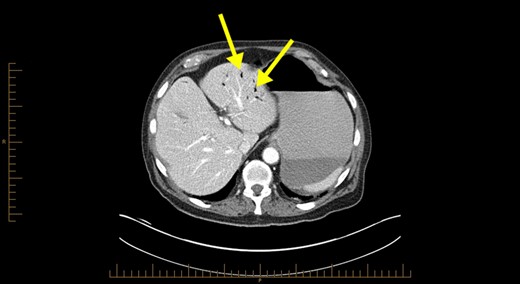

Blood investigations revealed a low haemoglobin of 104 g/l (115–165 g/l), low white cell count 1.56 × 109/l (4.0–10.0 × 109/l) with normal coagulation, liver function, lipase and lactate parameters. Competent tomography (CT) abdomen scan identified grossly thickened small bowel with a large amount of portal venous gas in liver (Figs 1 and 2). Like us, the radiologist was concerned these features were highly suggestive of small bowel ischaemia.

Computerized tomography abdominal axial section showing air within the hepatic portal veins (yellow arrows).

The pathophysiology of HPVG is unclear, but two hypotheses in the literature exist. The first states that factors such as mucosal barrier damage, bowel distension, increased intraluminal pressure and bacterial fermentation of carbohydrates in sepsis result in gas production [5]. The second theory is that gas-forming organisms present in the intestinal wall or venous system causes HPVG [5]. As seen in Fig. 1, HPVG is characteristically distributed as peripheral radiolucencies extending to within 2 cm of the liver capsule.